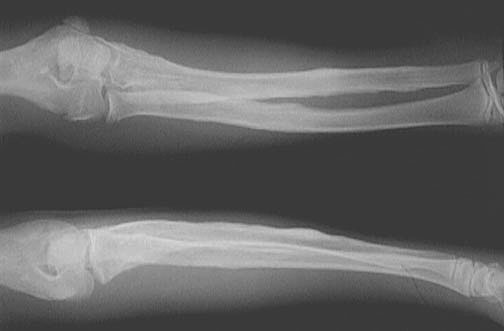

The condition depicted here is congenital familial osteomatosis. Multiple osteomas are present, giving the long bones a "bumpy" appearance.